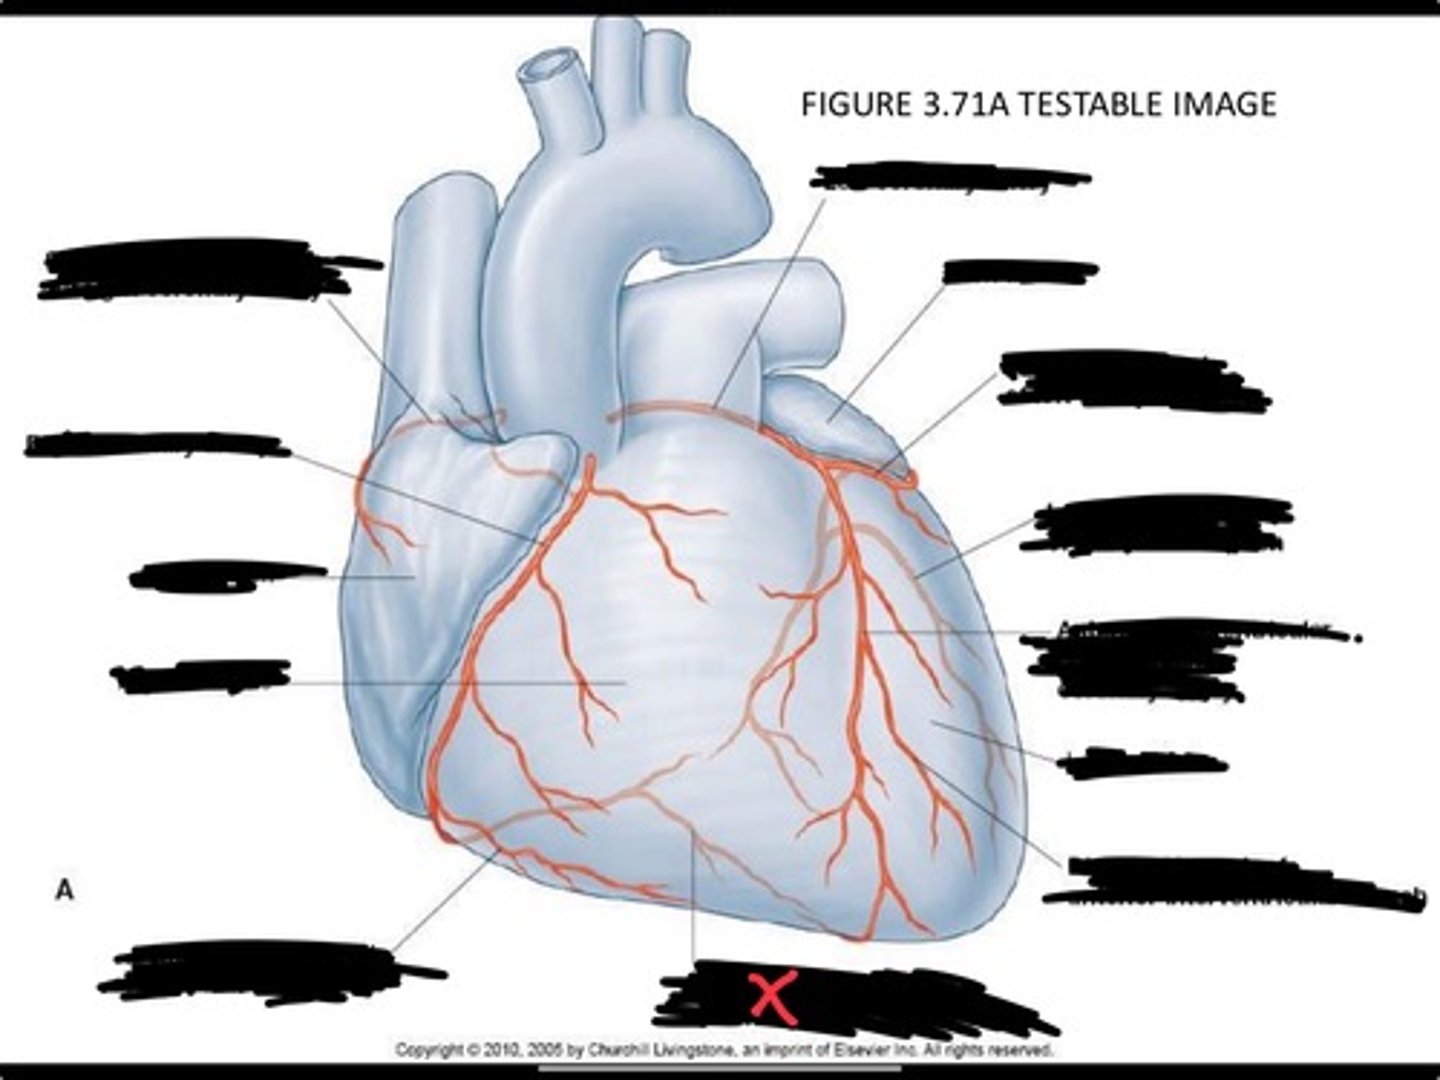

Pulmonary veins

Posterior interventricular branch of right coronary artery

Right arginal branch of coronary artery

Right ventricle

Right atrium

Right coronary artery

Sinu-atrial nodal branch of right coronary artery

Left coronary artery

Left auricle

Circumflex branch of coronary artery